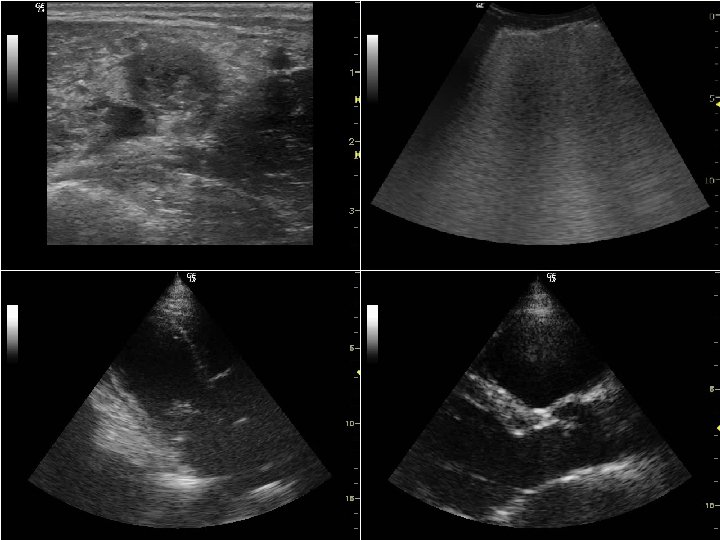

VENA CAVA INFERIORE Fluidoresponsività Condizione Parametro Soglia aumento IC > 15% pazienti VCI SN SP LR+ LRVentilazione invasiva 1 d. VCI (Dmax-Dmin) /Dmin Respiro c. VCI spontaneo 2 -Dmin) (Dmax /Dmax >18% 90% 9. 0 0. 11 >40% 80% 70% 4. 67 0. 35 d. VCI = indice di distensibilità cavale c. VCI = indice di collassabilità cavale 1. Barbier C, et al. Intensive Care Medicine 2004; 30: 1740 -6 2. Muller L, et al. Critical Care 2012; 16: R 188 -94

VENA CAVA INFERIORE ∆ misura AP PVC mm. Hg 100% > 50% 33 -50% 0 -33% 0 0 -5 5 -10 10 -15 15 -20 > 20

VENA CAVA INFERIORE ∆ misura AP PVC mm. Hg 100% > 50% 33 -50% 0 -33% 0 0 -5 5 -10 10 -15 15 -20 > 20 ∆ misura AP ∆ IC dopo carico < 18% > 18% Ventilazione meccanica NS > 15%

VENA CAVA INFERIORE ∆ misura AP PVC mm. Hg 100% > 50% 33 -50% 0 -33% 0 0 -5 5 -10 10 -15 15 -20 > 20 ∆ misura AP ∆ IC dopo carico < 18% > 18% < 40% > 40% Ventilazione meccanica Respiro spontaneo NS > 15%

ECO SEPSI VCI PAZIENTI IN RESPIRO SPONTANEO Riduzione insp VCI 100% Riduzione insp VCI < 33% Prex AD = 0 -5 mm. Hg Prex AD = 15 -20 mm. Hg Responsività ai fluidi SI Responsività ai fluidi (NO)

ECO SEPSI VCI PAZIENTI IN RESPIRO SPONTANEO Riduzione insp VCI 100% Riduzione insp VCI 0 % Prex AD = 0 -5 mm. Hg Prex AD = 20 -25 mm. Hg Responsività ai fluidi SI Responsività ai fluidi NO

ECO SEPSI LA FUNZIONE PRE-CARICO e POST-CARICO C • Nei pazienti con sepsi grave e shock settico si ha in genere una diminuzione del precarico dx e sn e una diminuzione del postcarico sn; il post-carico dx può aumentare in caso di polmoniti estese e di ARDS • Una VCI di calibro ridotto di base indica un’ipovolemia • Le variazioni di calibro della VCI sono ben correlate al precarico dx (e alla fluido-responsività) nei pazienti intubati e dipendenti dal ventilatore; la correlazione è meno buona nei pazienti in respiro spontaneo • Anche quando è difficile valutare a priori la responsività al carico volemico, con l’ecografia polmonare si può sempre valutare a priori la tolleranza al carico • Il VTD del VS è un indice del precarico sn

DIAFRAMMA • Scansioni trans-epatiche e trans-spleniche per visualizzare la cupola diaframmatica – a dx per via sottocostale tra l’emiclaveare e l’ascellare anteriore – a sn per via intercostale tra l’ascellare anteriore e l’ascellare media • Orientamento della linea M-mode ortogonale rispetto alla cupola diaframmatica • Valutazione dell’escursione diaframmatica cranio-caudale • Valori normali (mm) M F – inspirazione tranquilla – ispirazione massimale 18 ± 4 70 ± 10 16 ± 4 60 ± 10